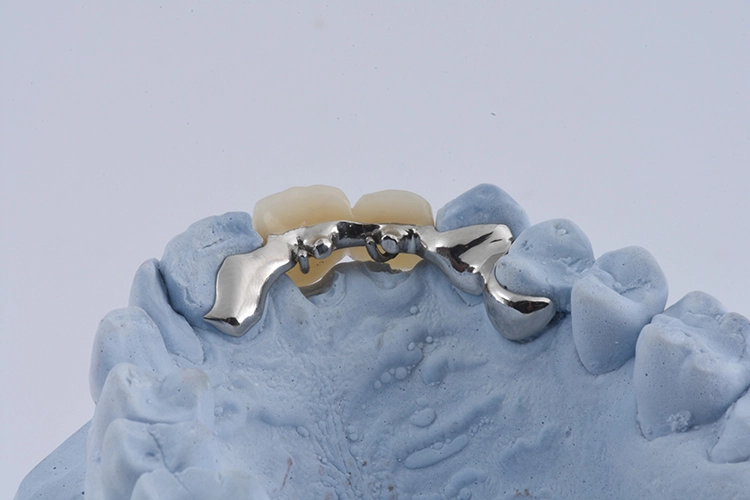

Ihr wurden die verschiedenen Behandlungsmöglichkeiten erklärt. Die Patientin wünschte sich den Erhalt der eigenen Zähne. Aufgrund der Breite der Lücke und schwierig zu schienender Situation entschieden wir uns für eine kieferorthopädische Extrusion der beiden Wurzelreste.

Dr. Blume